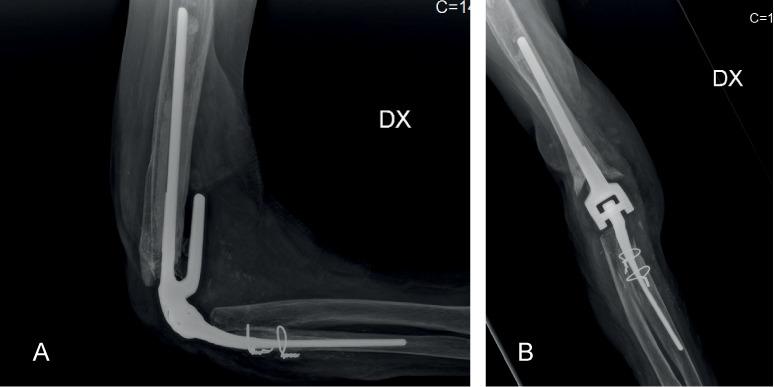

Soft tissue loss around  the elbow, with tendons, nerves and bone exposure,  represents a challenging condition, often requiring a complex and accurate surgical reconstruction. Inadequate repair of soft tissue defects may in fact compromise further reconstructive orthopedic procedures, including  osteosynthesis and joint replacement. A correct reparative sequence of these lesions usually starts with an appropriate debridement and removal of all non-viable and infected tissues, followed by soft tissues management through plastic and reconstructive techniques. Here we present a case report, showing a successful surgical solution, using a local muscular flap. The results are discussed in light of their functional and medico-legal implications, considering the frequent occurrence of partial functional recovery, the disabling impact on social and work activities and the aesthetic sequelae of these lesions, even in spite of a successful treatment.

肘部周围软组织缺失,伴有肌腱、神经和骨外露,是一种极具挑战性的病症,往往需要复杂而精确的外科重建。软组织缺损的修复不当实际上可能会影响进一步的重建骨科手术,包括骨内固定和关节置换。这些损伤的正确修复顺序通常首先进行适当的清创术,清除所有无活力和感染的组织,然后通过整形和重建技术处理软组织。我们在此报告一例病例,采用局部肌瓣成功实施了手术治疗。考虑到部分功能恢复频繁、对社会和工作活动的致残影响以及这些损伤的美容后遗症,即使治疗成功,我们也将根据其功能和医学法律方面的影响对结果进行讨论。